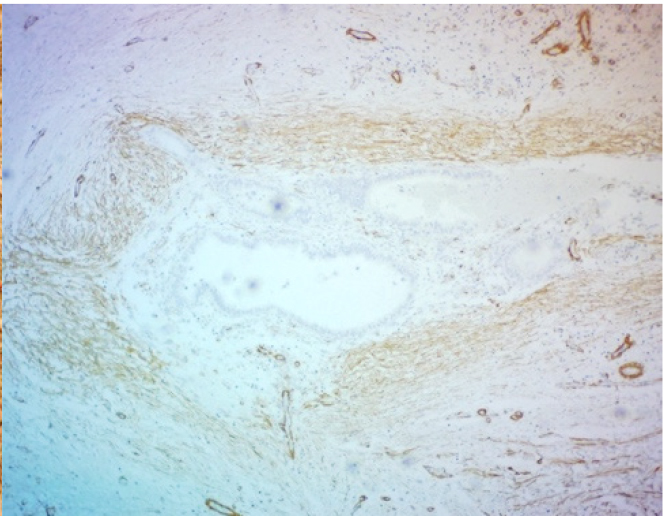

ИГХ-исследование выявило положительную экспрессию гладкомышечного актина в фокусах фиброза вокруг и между очагами экстрагенитального эндометриоза. Гладкомышечный актин экспрессировался в миофибробластах, концентрически расположенных вокруг эндометриоидных гетеротопий по типу «муфт» (рис. 3).

Рис. 3. Экспрессия α-SMA при эндомет-риозе послеоперационного рубца. ИГХ, ув. ×200

Очаговая экспрессия α-SMA была обнаружена в цитогенной строме очагов экстрагенитального эндометриоза в концентрических пролифератах миофибробластов по типу микроскопических лейомиом. В мышечном слое кишки наблюдалась положительная экспрессия α-SMA, которая повторяла ход мышечных волокон, деформируя стенку кишки в местах локализации очагов эндометриоза (рис. 4).

Рис. 4. Экспрессия α-SMA при эндометриозе толстой кишки. ИГХ, ув. ×200